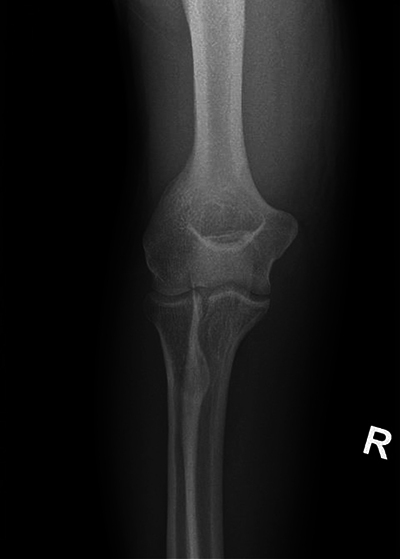

教学要点:强调在肌肉骨骼超声中识别镜像伪影的重要性,以避免误诊、不必要的干预和额外的诊断程序,从而导致患者焦虑、医疗费用增加和潜在的伤害。

Teaching point: To emphasize the importance of recognizing mirror image artifacts in musculoskeletal ultrasound to avoid misdiagnosis, unnecessary interventions, and additional diagnostic procedures that can lead to patient anxiety, increased healthcare costs, and potential harm.